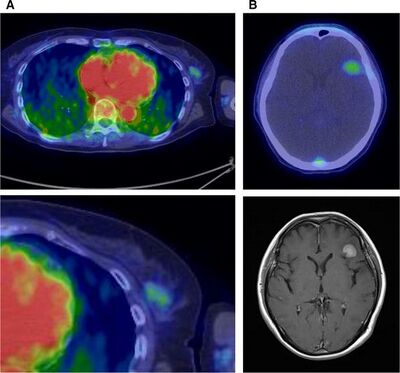

HER2 PET Imaging [7]

HER2, which is overexpressed in 25 to 30 percent of breast cancer patients, is involved in tumor cell survival, proliferation, maturation, metastasis, and angiogenesis. Trastuzumab, an antibody against HER2, is widely used in targeting HER2. HER2 expression is determined using immunohistochemistry (selectively imaging antigens by exploiting antibodies binding specifically to antigens in tissue), or fluorescence. However, these techniques cannot be used when the tumor cannot be easily accessed for a biopsy. Additionally, HER2 expression can vary during the course of the disease. In order to avoid these complications, PET imaging can be used to non-invasively determine HER2 expression. Currently, HER2 antibodies have been labeled with 124I, 86Y, 76Br, 89Zr, and 64Cu for PET imaging. Use of 64Cu-trastuzumab allowed for primary tumor lesions larger than 2 centimeters in diameter, and metastatic brain lesions larger than 1 centimeter in diameter to be visualized (Figure 7).